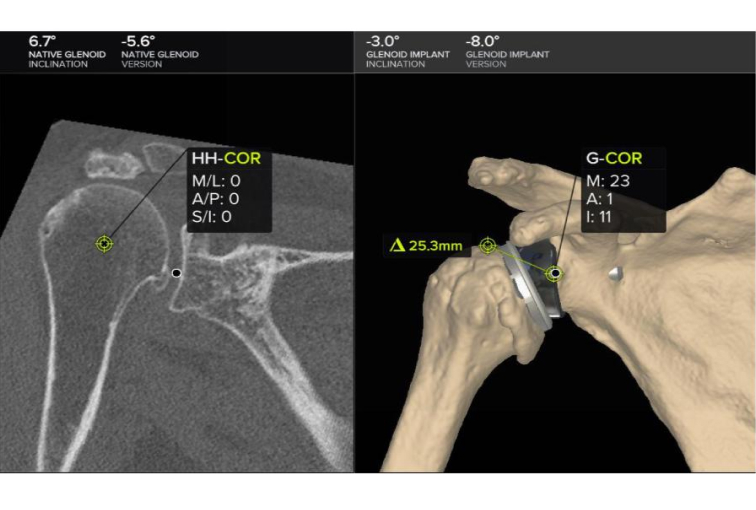

Seeking the blessings of His Holiness Jagadguru Dr. Sri Shivaratri Rajendra Mahaswami ji and offering our humble pranams to His Holiness Jagadguru Sri Shivarathri Deshikendra Mahaswami ji, JSS Hospital has achieved a historic milestone in healthcare. For the very first time in Mysuru, the Department of Orthopedics successfully performed a Reverse Total Shoulder Arthroplasty (RTSA) using state of the art Virtual Implant Positioning (VIP) technology by Arthrex.

Reverse Total Shoulder Arthroplasty is a sophisticated surgical solution designed for patients with severe shoulder dysfunction, particularly when conventional shoulder replacement proves ineffective. Individuals suffering from persistent pain, difficulty with daily activities such as combing hair or reaching the back, and pseudo-paralysis caused by rotator cuff insufficiency can benefit significantly from this approach. In this technique, the shoulder’s natural ball-and-socket orientation is reversed, where the glenoid socket becomes the humeral head and the humeral head assumes the role of the socket.

This modification empowers the deltoid muscle to compensate for damaged rotator cuff muscles, thereby restoring function and improving quality of life.